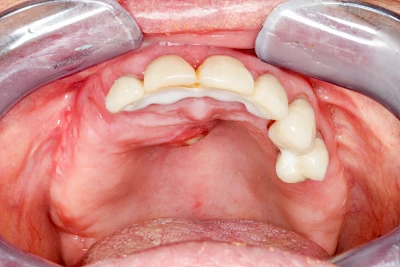

Früher wurden im Unterkiefer mitunter Brücken zum Ersatz fehlender Zähne als sogenannte "Schwebebrücken" gestaltet. Die Idee dabei war, dass man die Brücke insgesamt besser reinigen kann. Allerdings war das für die Patienten mitunter irritierend für die Zunge und vor allem beim Essen gewöhnungsbedürftig. Teilweise haben sich hier reaktiv Vakatwucherungen der Kieferkammschleimhaut gebildet und den Raum unter der Brücke wieder verschlossen.